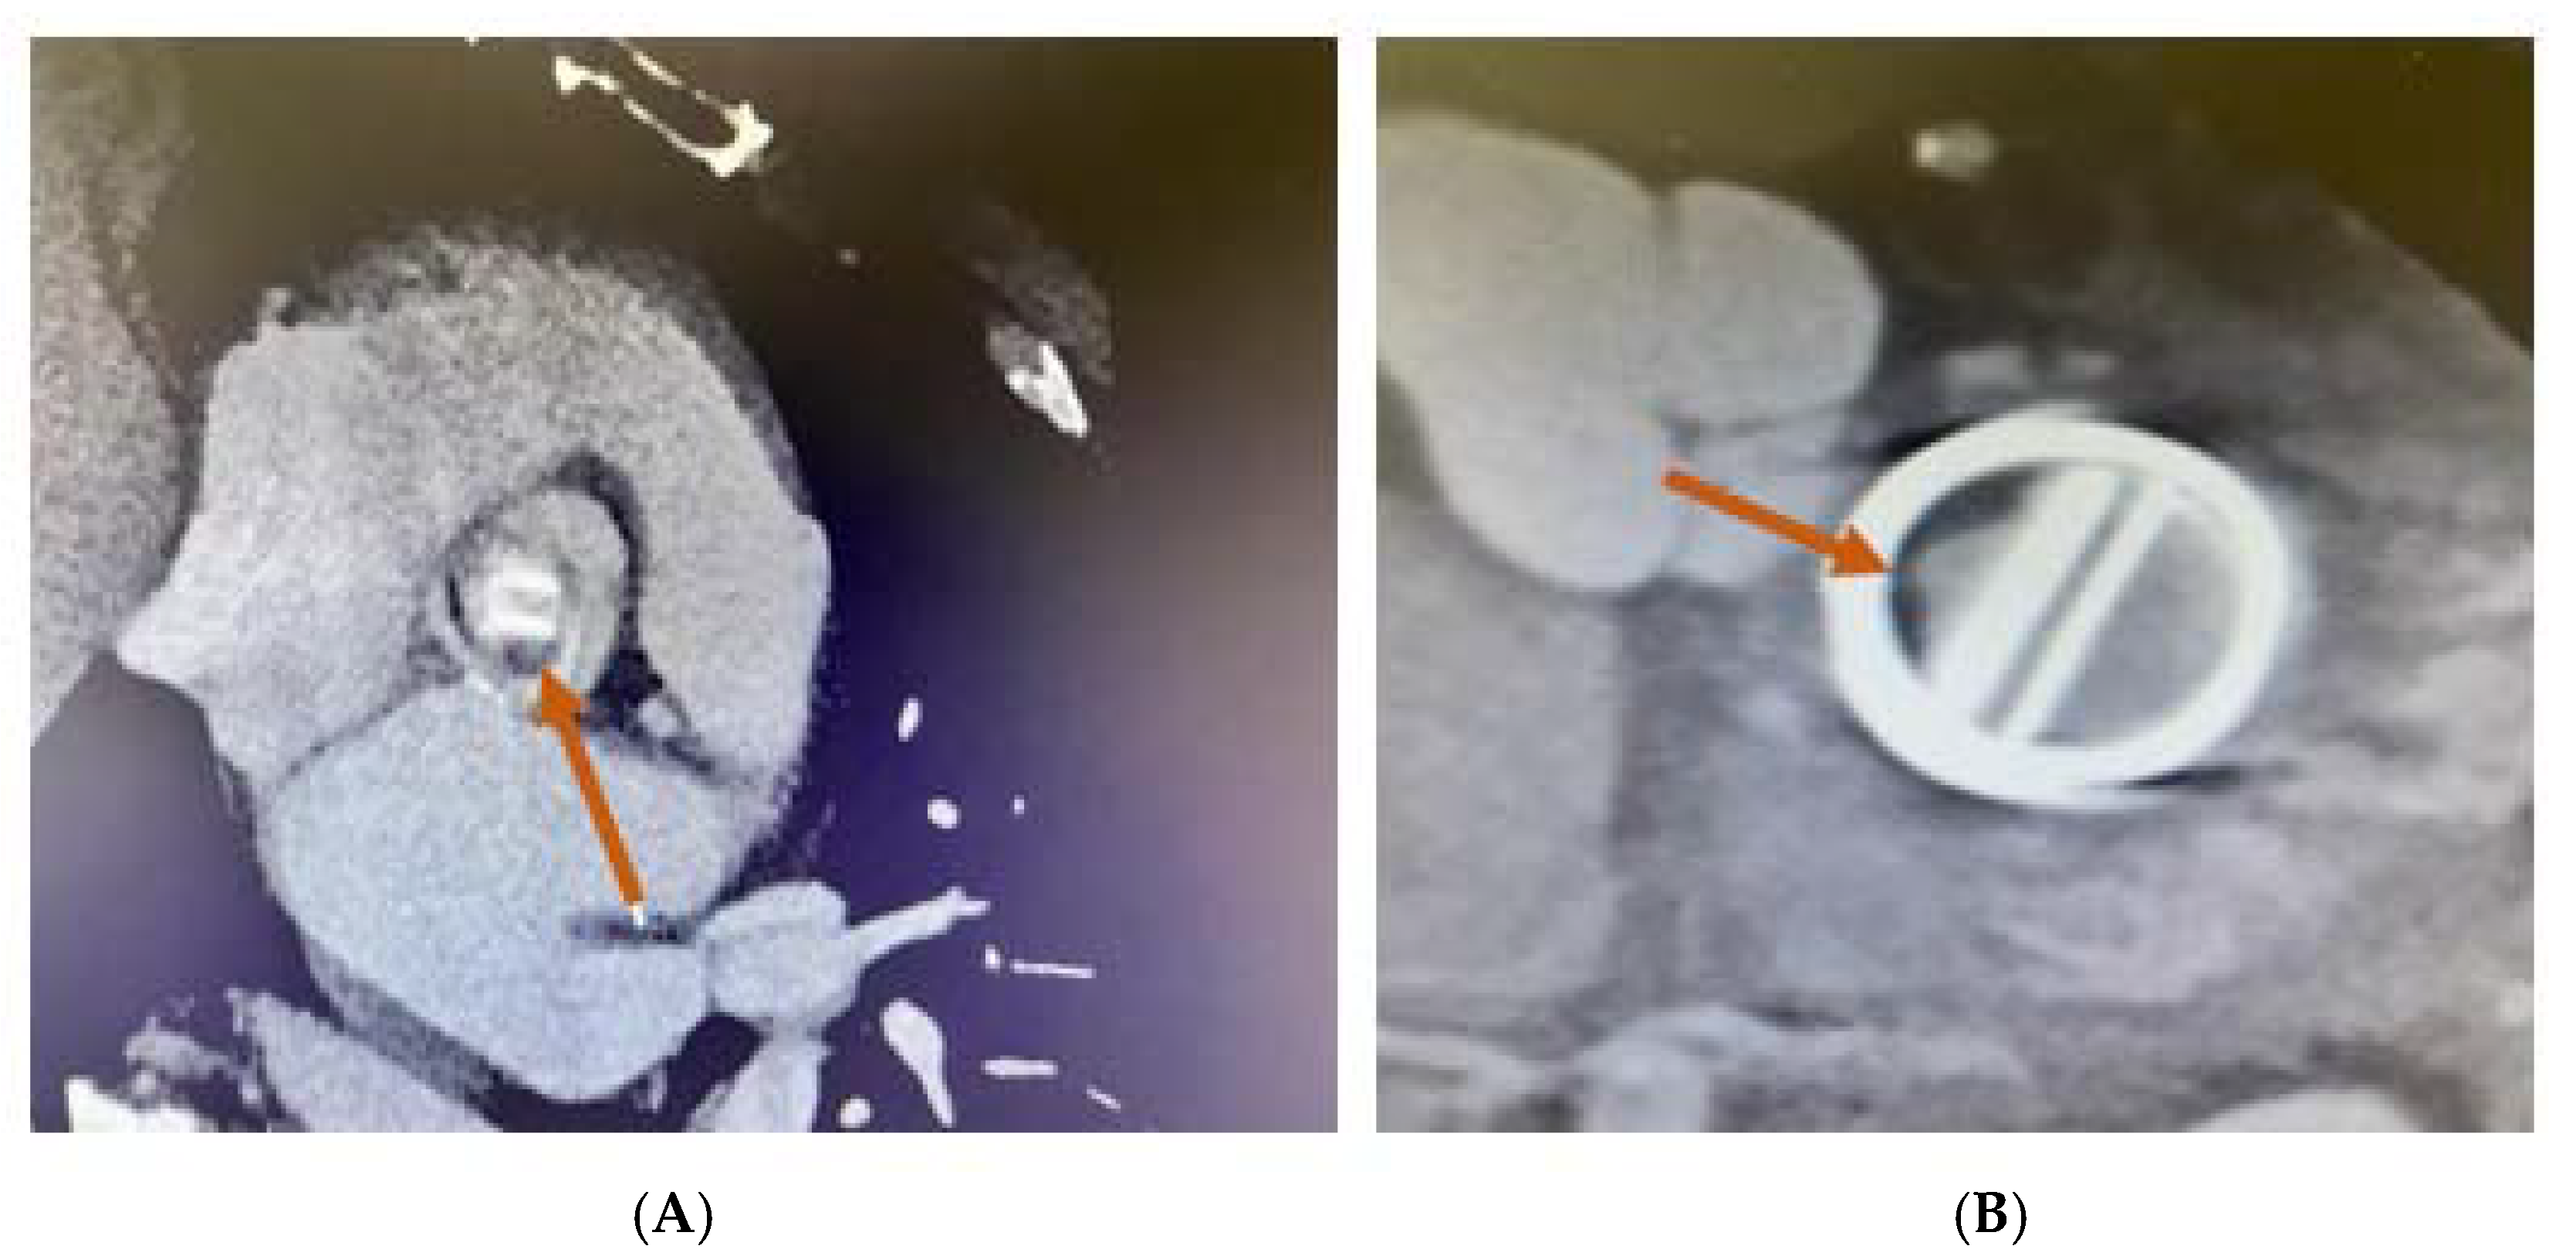

The moment of the lesion development, as well as its location at the level of the prosthesis, are important factors in establishing its etiology. In the first year following the valve implantation, thrombus commonly develops on the aortic and left ventricular outflow tract (LVOT) sides (Figure 11).

Figure 11.

MDCT. Thrombus on (A) aortic mechanical valve prosthesis (arrow). (B) Mitral mechanical valve prosthesis (arrow).

The pannus, which is exclusively observed on the LVOT side, typically develops over a longer duration, frequently over a year [45].

In the case of mechanical MVT, MDCT facilitates the evaluation of the valve’s opening and closing angles (Figure 12) and the characterisation of masses attached to the prosthesis and the surrounding tissues [45].

Figure 12.

MDCT. Aortic bidisc mechanical prosthesis in diastole and systole.